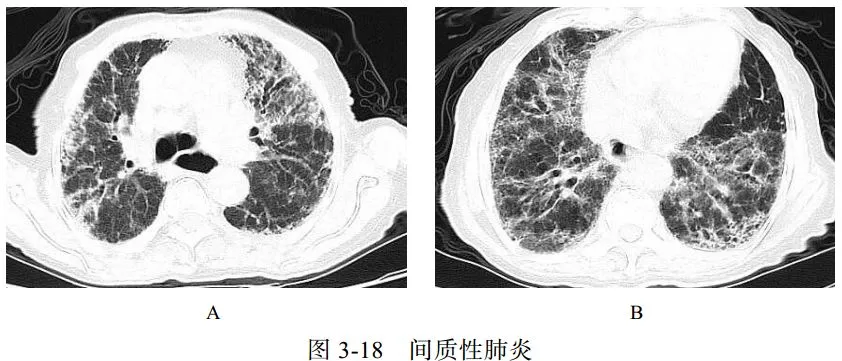

(四)间质性肺炎

肺间质纤维化性疾病包括一系列导致肺间质进行性纤维化的原发性或继发性结缔组织疾病,原发性主要为特发性肺间质纤维化,继发性主要包括系统性红斑狼疮、干燥综合征、类风湿关节炎等。特发性肺间质纤维化、系统性红斑狼疮、干燥综合征三种病变在影像学上表现相似,属于典型的“同影异病”,均表现为肺间质纤维化改变。细菌和病毒均可以引起间质性肺炎

影像学表现:两肺支气管血管束增多,网格状及小点状影,周围夹杂多发蜂窝状囊状影、肺气肿及牵拉性支气管扩张,相应胸膜下小叶间隔增厚(图 3-18)